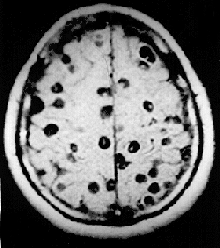

Im Gehirn des Patienten befindet sich eine Vielzahl von Finnen (MRT-Aufnahme)[13]

Eine Infektion mit Bandwürmern ist nur über die Aufnahme eines mit Bandwurmlarven (Finnen) befallenen Stück Fleisches oder Fisches möglich, das unvollständig gegart wurde. Die Larven befallen verschiedene Organe, wie beispielsweise das Gehirn, und die Muskulatur. Dies kann zu Entzündungen mit Gewebeverkalkungen und Krampfanfällen führen.[14]